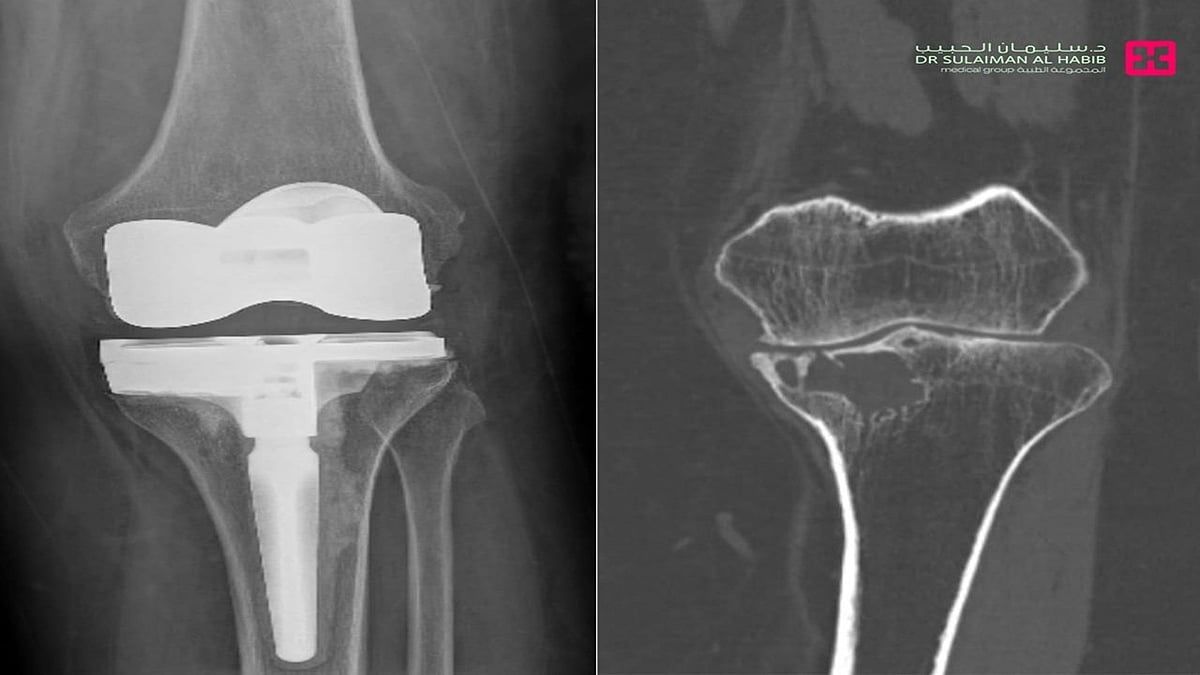

وقال د. أنس أنه عند وصول المراجعة للعيادة، تم الإستماع إلى شكواها والإطلاع على تاريخها المرضي وإجراء الفحص السريري، وتبين معاناتها من صعوبة المشي والحركة والشعور بنوبات من الألم .على الفور تم إخضاعها لفحوصات طبية دقيقة بالتصوير المقطعي C.T Scan والأشعة السينية الرقمية Digital X-Rays والتحاليل المخبرية.

مشيراً إلى أن نتائج الفحوصات كشفت عن وجود ورم في عظمة الساق، مع خشونة شديدة في الركبة. وتم أخذ خزعة من الورم تحت اشراف طبيب الأشعة التداخلية، إذ تم تشخيص الورم بورم دموي حميد. مفيداُ بأنه تم تكوين فريق طبي من استشاري جراحة العظام والأورام والأشعة التداخلية والتخدير والعناية المركزة، وعقب دراستهم لكامل نتائج الفحوصات، تم اتخاذ القرار بالتدخل الجراحي العاجل،وذلك للحيلولة دون إصابة المراجعة بمزيد من الأعراض والمضاعفات الحادة، والمتمثلة في كبر حجم الورم وانتشاره في مواضع أخرى بالجسم.

موضحاً بأنه تم إخضاع المراجعة لجراحة دقيقة استغرقت ساعتين تحت التخدير العام، وتم فيها كحت الورم واستئصاله بالكامل، واستبدال مفصل الركبة في عملية معقدة ، وترميم الفجوة بواسطة دعامات خاصة.